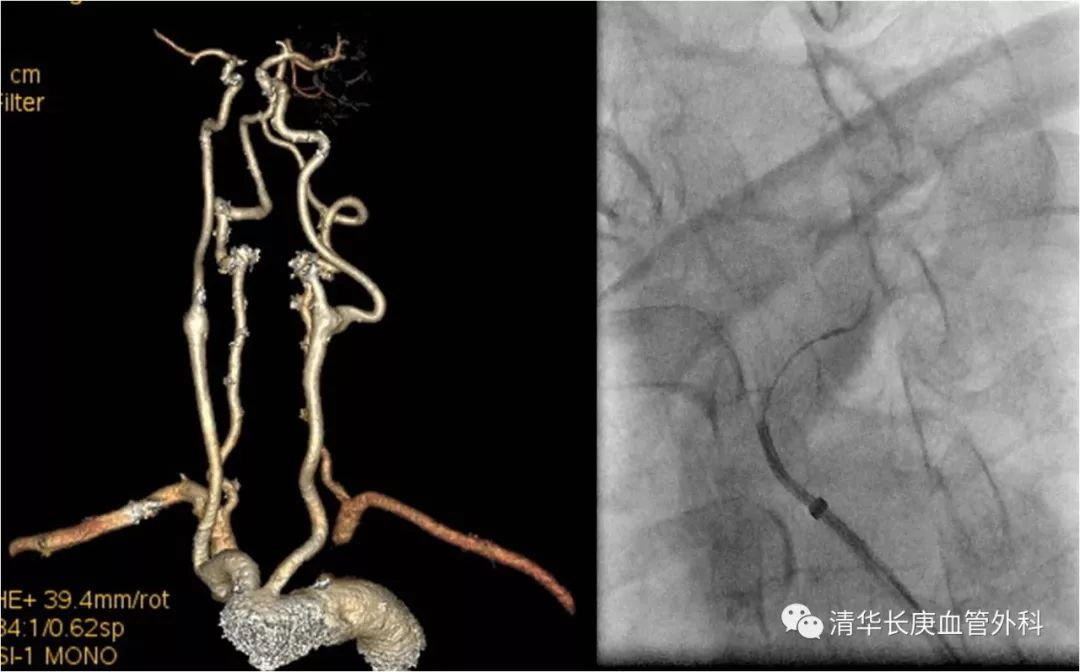

赵克强副主任医师,以典型病例录播形式,向学员们分享了弓上动脉病变的治疗,包括锁骨下动脉闭塞、复杂弓型颈动脉支架的入路建立、多发病变、串联病变的治疗策略,以及弓上病变围术期管理、术中技巧、常见并发症及预防措施;学员们积极踊跃、畅所欲言、沟通心得,对弓上病变的诊治有了进一步的认识、体会。

锁骨下动脉闭塞,长鞘+椎管+CXI+V18同轴系统通过病变

双导丝技术

不友好弓型的入路建立